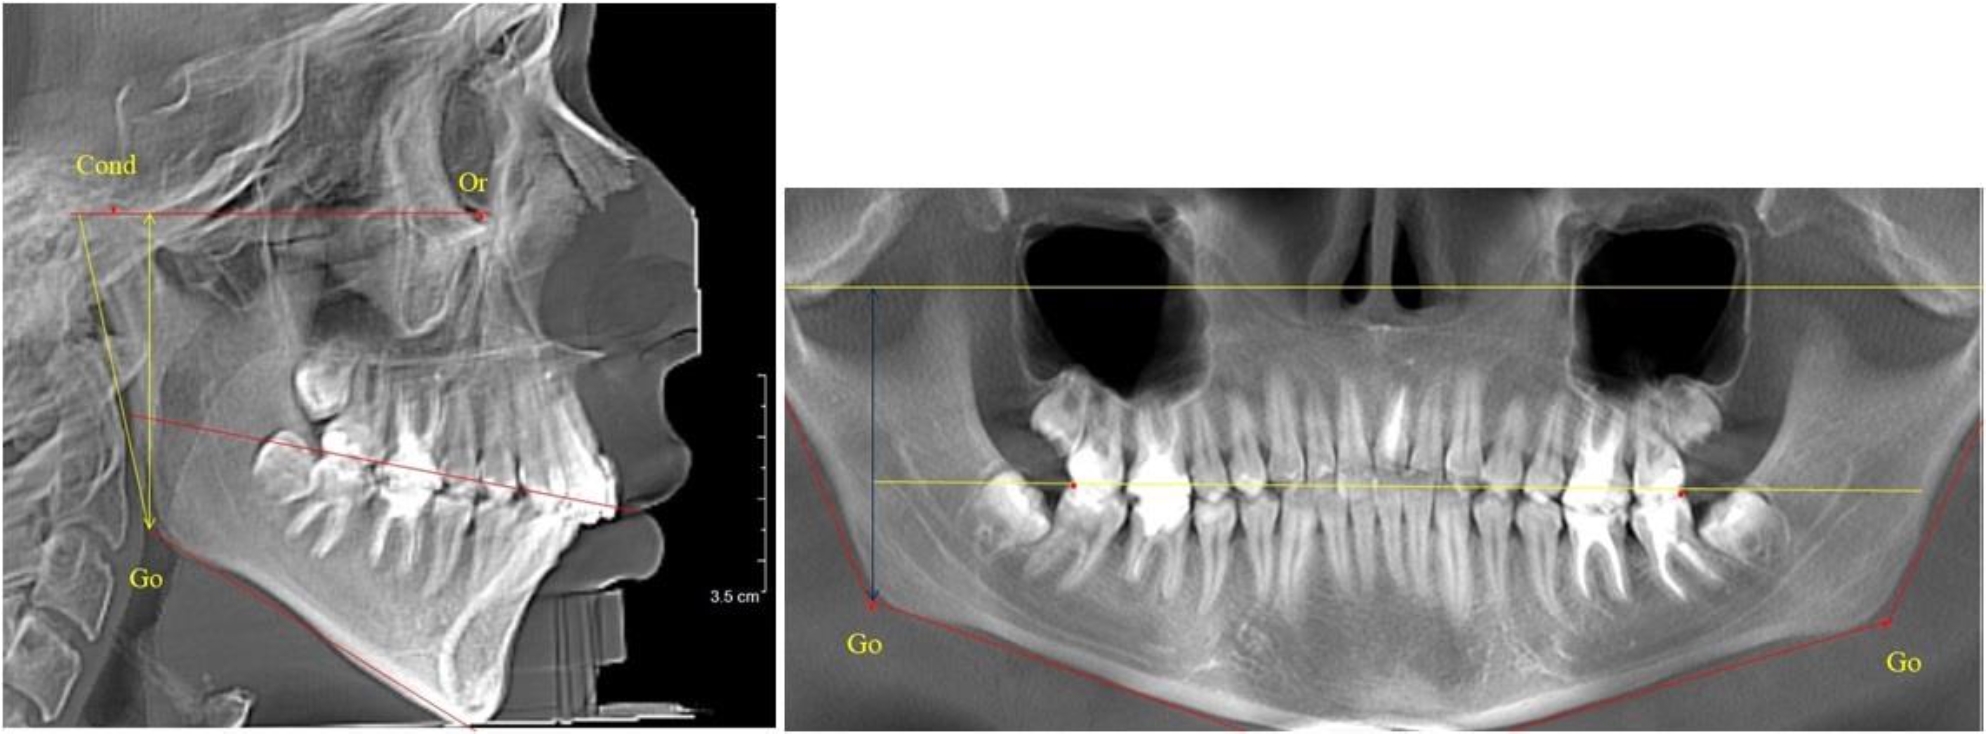

В 5-й группе были проанализированы 14 комплектов рентгенограмм, что составило (13,21 ± 3,29) % от общего числа. На всех рентгенограммах отмечен очередной этап подъема высоты прикуса, обусловленный прорезыванием вторых постоянных моляров. Окклюзионная линия делила ветвь на два отдела (рис. 5).

Рис. 5. ТРГ и ОПТГ пациента после смены молочных зубов и прорезывания вторых постоянных моляров

Высота ветви у детей 5-й группы составляла (62,87 ± 3,62) мм, что было достоверно больше, чем у детей других групп (р ˂ 0,05). При этом высота верхней окклюзионно-суставной части была (40,23 ± 2,01) мм, а нижней – (22,64 ± 1,78) мм. Высота верхней части была вдвое больше нижней, что и определяло особенности соразмерности частей ветви нижней челюсти в анализируемый возрастной период.

Относительные показатели соразмерности частей ветви нижней челюсти показали, что отношение высоты верхней части ветви к нижней в среднем составляло 1,78 ± 0,18. Отношение общей высоты ветви к верхней ее части составляло 1,56 ± 0,12, а отношение общей высоты ветви к нижней ее части было 2,78 ± 0,14, что и определяло особенности соразмерности частей ветви нижней челюсти в анализируемый возрастной период.

Таким образом, прорезывание постоянных зубов и смена молочных зубов постоянными изменяло не только высоту ветви нижней челюсти, но и изменяло соотношение ее частей, разделенных условной линией, являющейся продолжением окклюзионной линии рентгенограммы. Наиболее вариабельной структурой ветви являлась верхняя ее часть с суставным отростком. Окклюзионно-альвеолярная часть коррелировала с высотой зубочелюстных сегментов нижней челюсти.